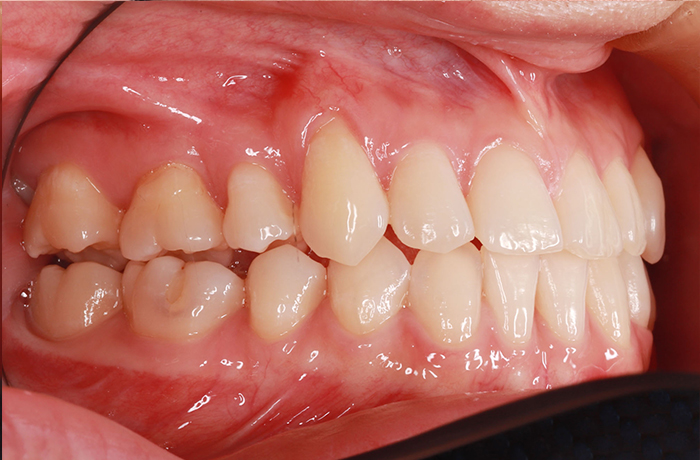

治療前

before

患者の症状 叢生、正中のずれ、上顎左右側切歯の口蓋側転位(交叉咬合)

治療方法 非抜歯で、マウスピース型カスタムメイド矯正歯科装置(インビザライン)による矯正

歯列弓を拡大することで非抜歯を可能にしました。

治療結果 側切歯の交叉咬合は解消、上下正中のずれも改善し咬み合わせが良くなりました。